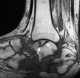

Posttraumatic osteonecrosis

An occult fracture is a fracture that is not readily visible, generally in regard to projectional radiography ("X-ray"). Radiographically, occult and subtle fractures are a diagnostic challenge. [Source: Wikipedia ]